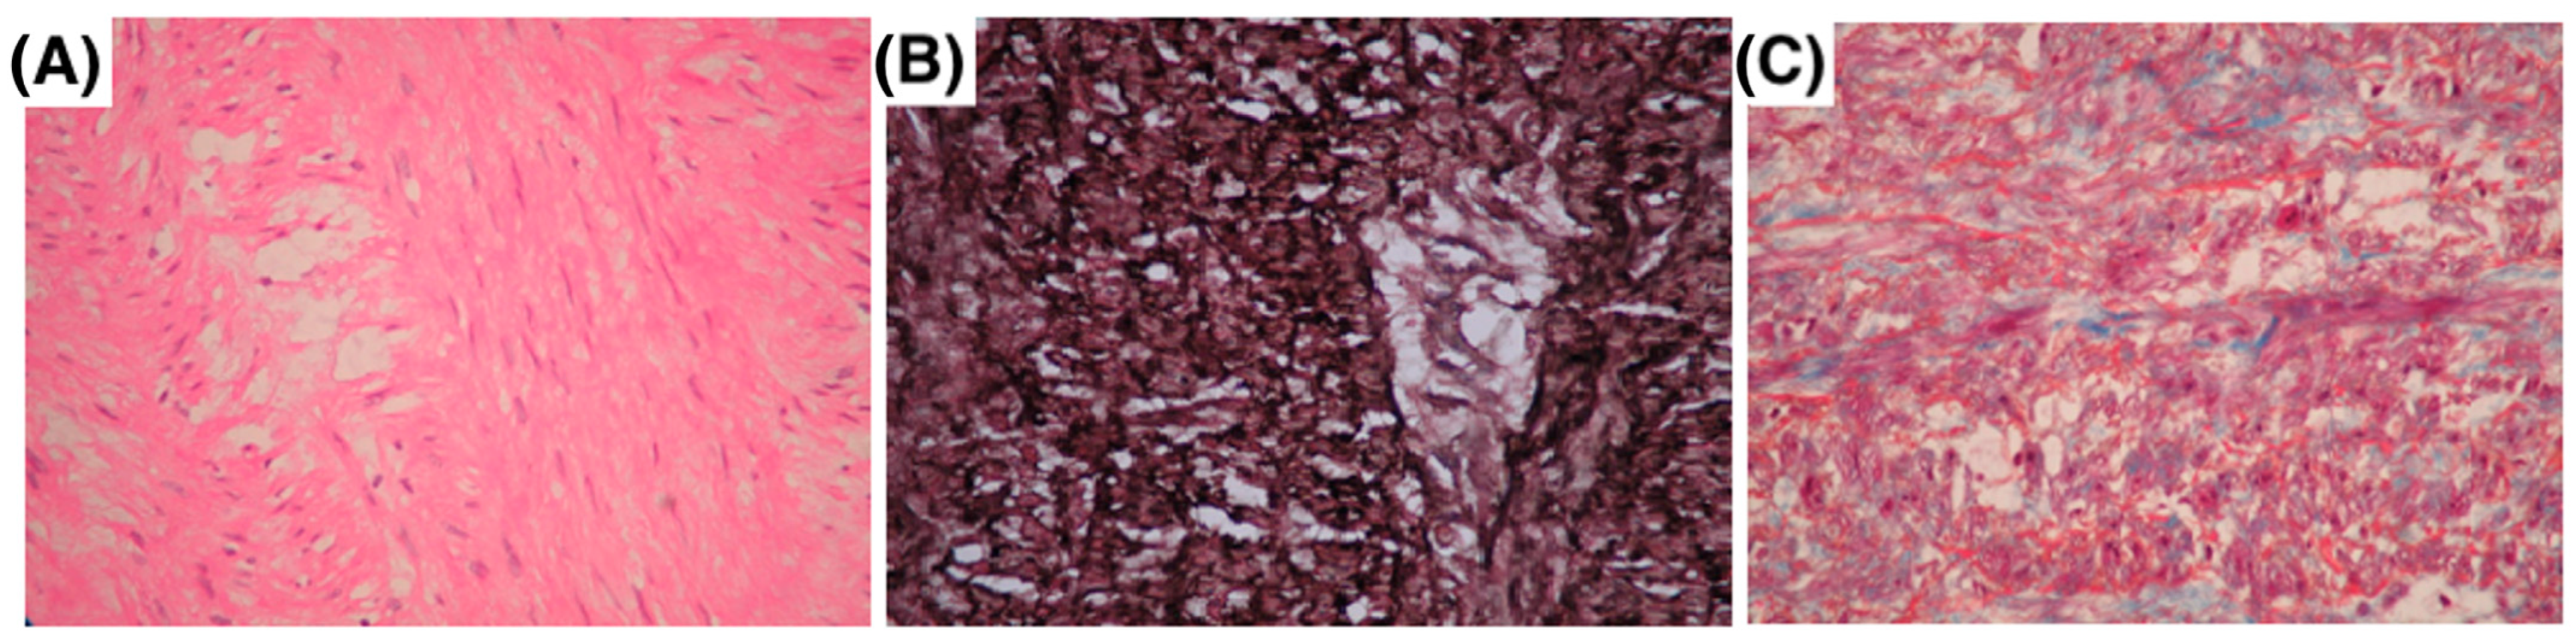

4.6. Histology

4.8. mRNA Extraction and Quantification by RT-qPCR